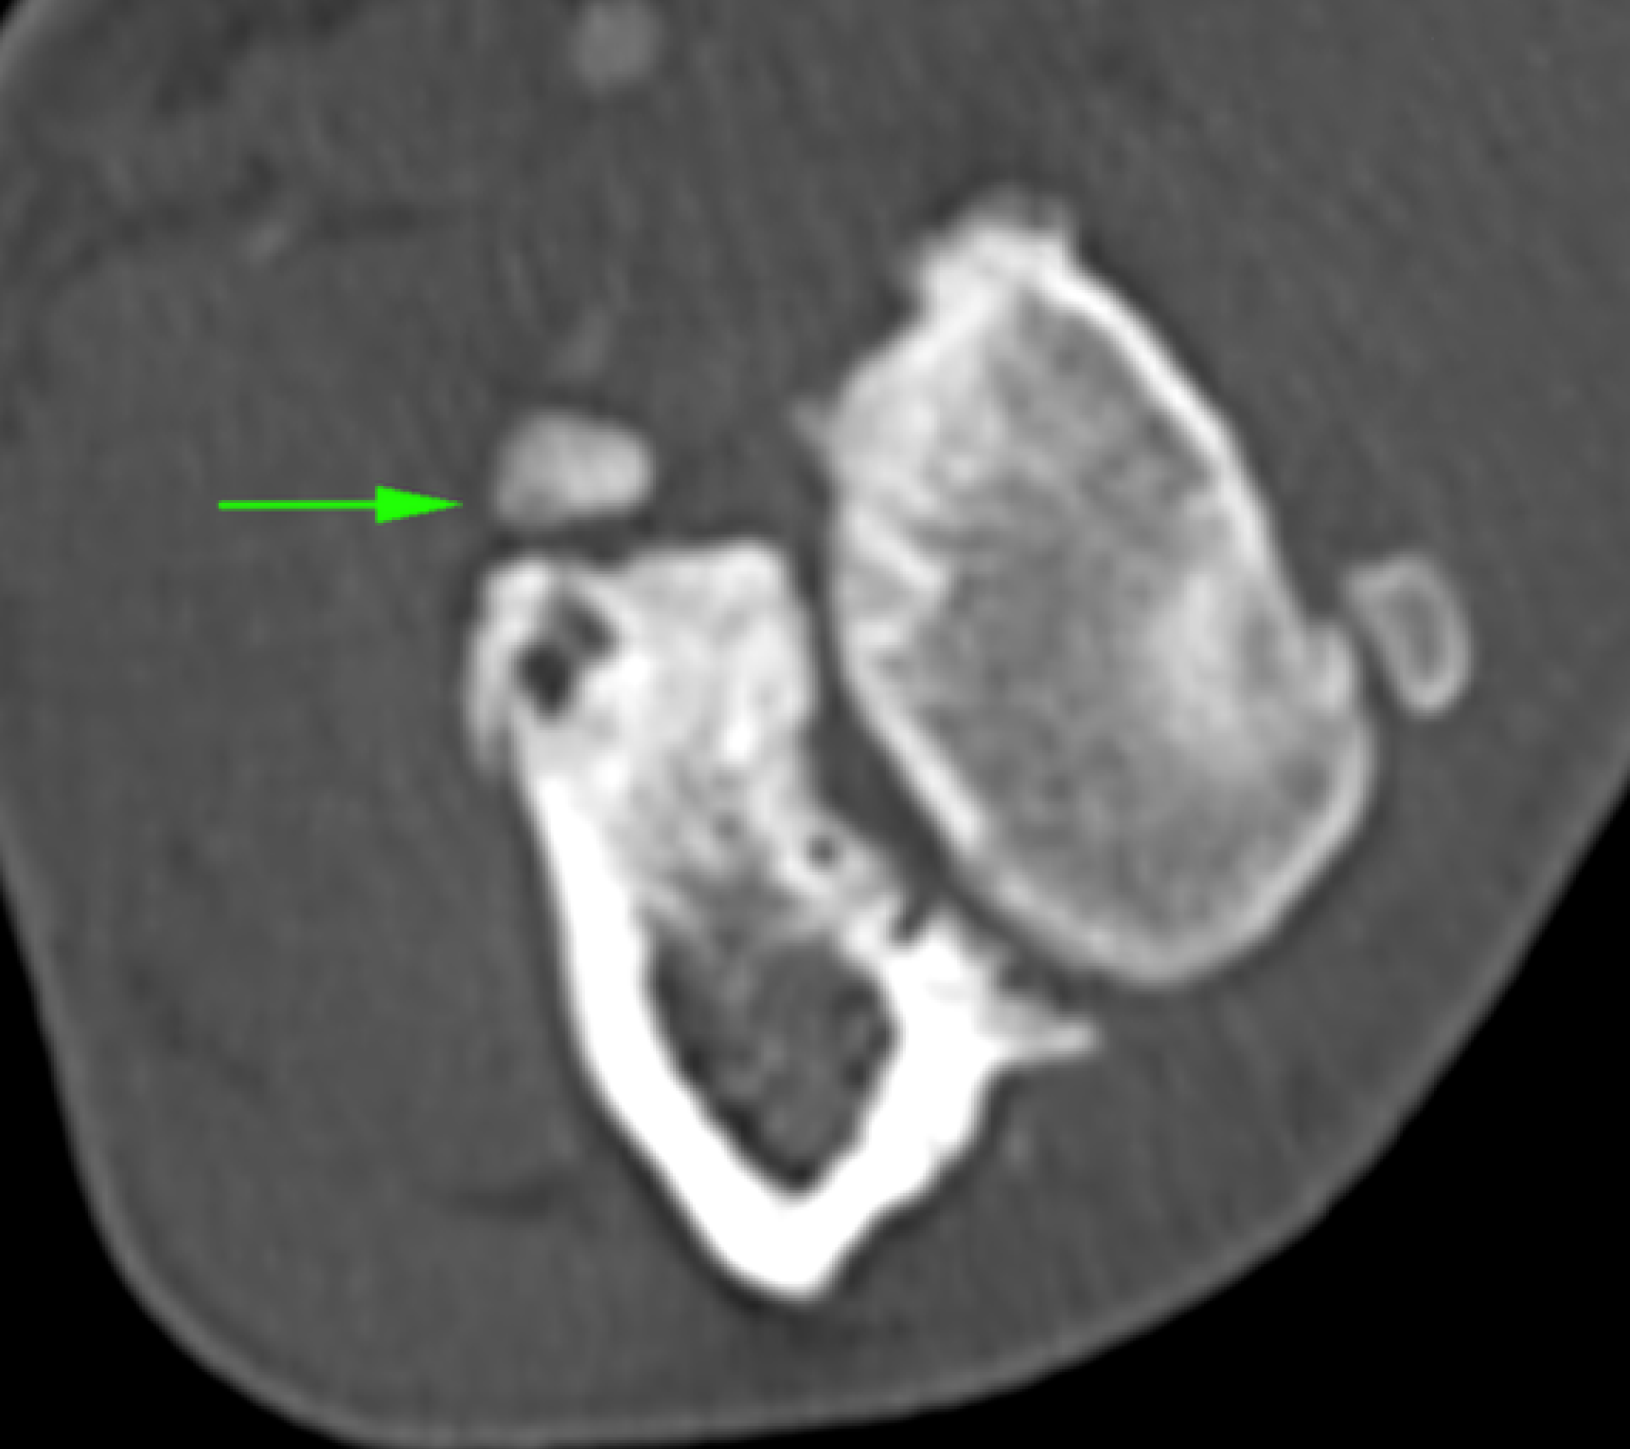

La Tomografía computerizada (CT) o TAC es la técnica por imagen de elección. El procesado avanzado de la imagen nos permitirá visualizar finos cortes de la anatomía y detectar pequeñas lesiones (por ejemplo, fragmentación del proceso coronoides), las cuales son difíciles de diagnosticar en radiografías convencionales.

La artroscopia (introduciendo una pequeña cámara dentro de la articulación) supone un apoyo diagnóstico al TAC, ya que permite visualizar el cartílago articular (cosa que no hace el anterior). Al mismo tiempo permite tratar la mayoría de lesiones asociadas a la patología (retirar fragmentos, etc.)